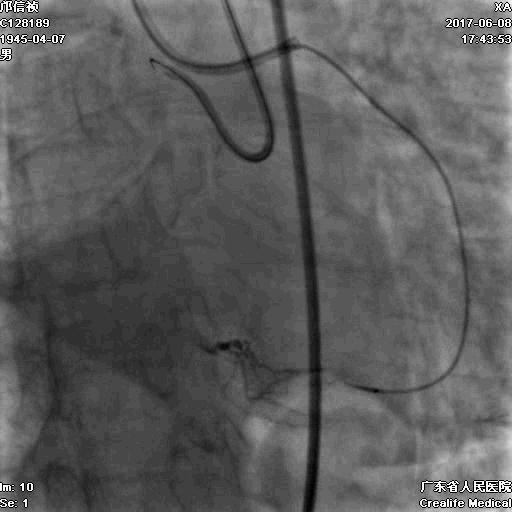

RRA:6F AL0.75 GC –RCA;

RFA:7F XB 3.5 GC—LCA 150cmcorsair

正向130cmFinecross微导管支持下尝试送PILOT150、Gaia 2导丝无法通过RCA闭塞段

SION导丝通过侧枝

逆向导丝:更换Gaia2

正向导丝:Gaia2,PILT150

正向导丝knuckle

2.5*15mm球囊扩张,逆向导丝尝试,但未能进入正向GC

1.正向2.5*15mm球囊扩张,Reverse CART

2.Guidezilla延长导管辅助下,逆向导丝进入正向GC

1.更换RG3导丝

2.GC送入普通导丝,保护LM